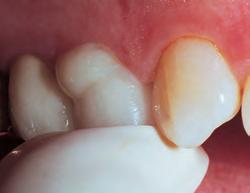

Opalescence whitening gel is recommended for whitening discolored teeth prior to placement of composite, veneers, and/or crowns. It is effective in breaking down some or all internal tooth discolorations due to factors such as congenital, systemic, pharmacologic, traumatic, etc., as well as aging. It is successful with staining from fluorosis and tetracycline.3,6

Before whitening.

Before whitening; new restorations are planned.

After 8 days of treatment with Opalescence PF 16% whitening gel, every day for 3 hours.

After 6 days of treatment with Opalescence PF 10% whitening gel, every night for 8 hours. New composite restorations in place.